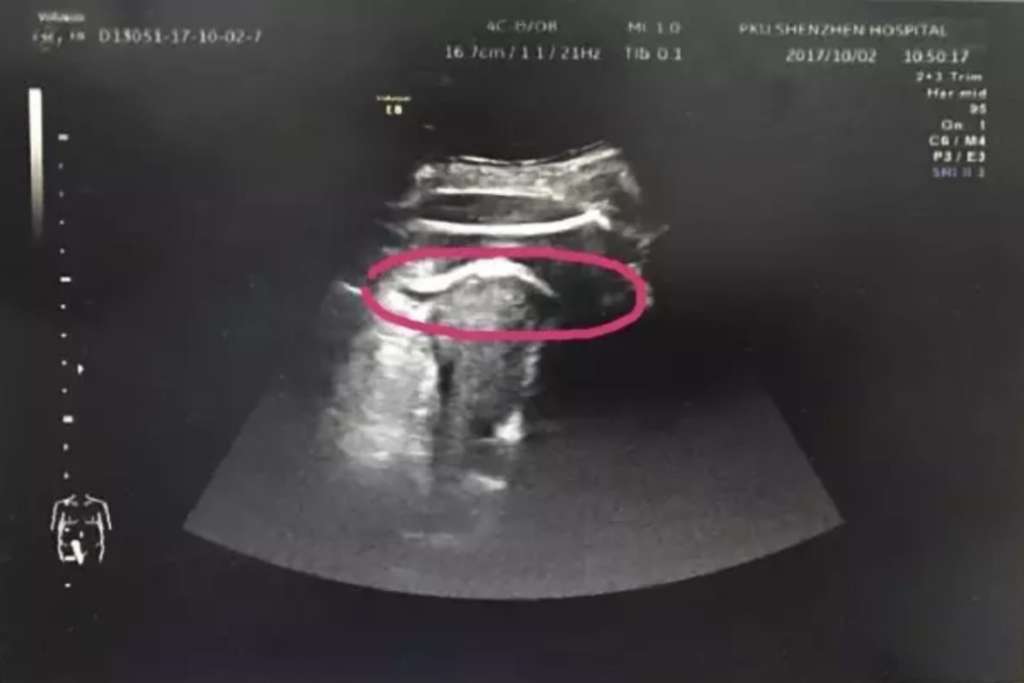

Upon going to Peking University Shenzhen Hospital, doctors performed an ultrasound and discovered the baby had “kicked through” the uterus wall, and her thighs were stuck.

Doctors were able to deliver the child via C-section in just 10 minutes. During the delivery, doctors discovered the 7 centimeter break in her uterus.